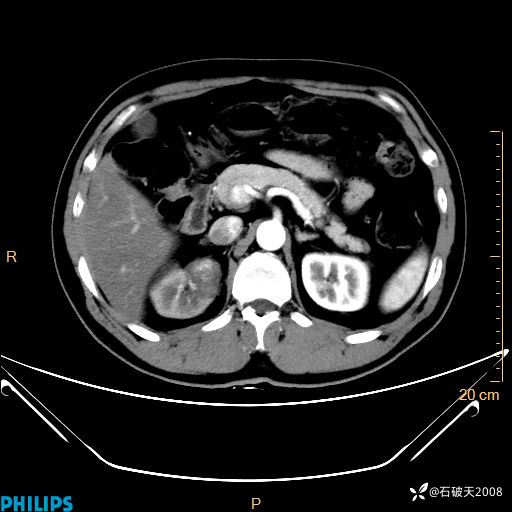

MIP